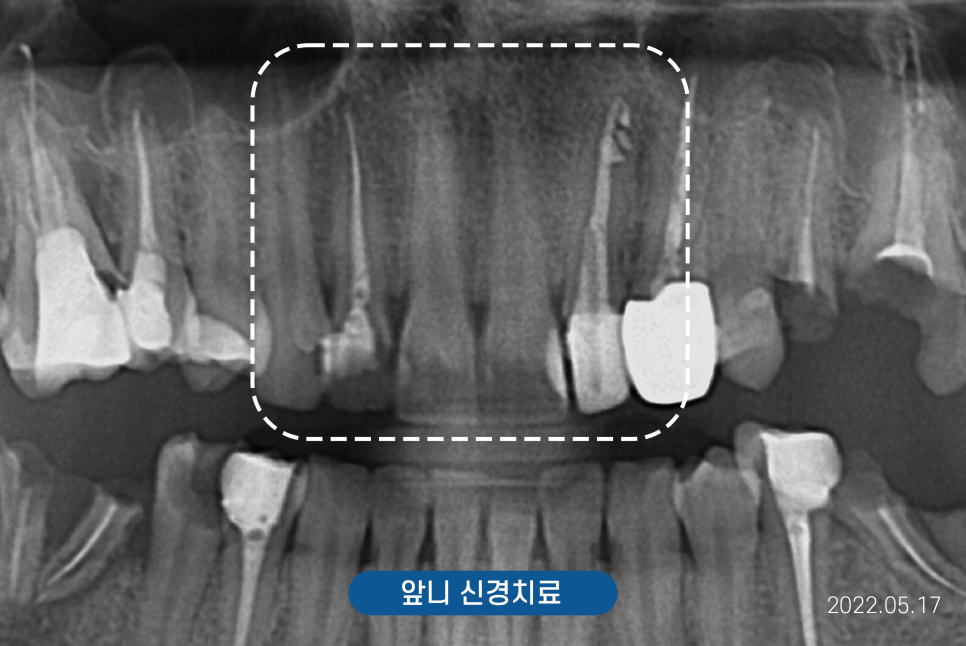

위 사진 X-ray를 보시면

치아 뿌리가 흰색으로

채워져 있는데

흰색은 신경 제거 후

약제를 넣어 하얗게 보이는 것입니다.

신경을 제거한 치아는

물없는 나무처럼 푸석하기에

크라운을 씌우지 않으면 파절가능성이 있는데,

앞니 충치까지 생겨 크라운을

씌워야하는 상황이었어요.

약간의 치아배열의 삐뚤함이 있어

심미보철을 제작하면서

배열을 올바르게 들어가자고 설명드렸습니다.